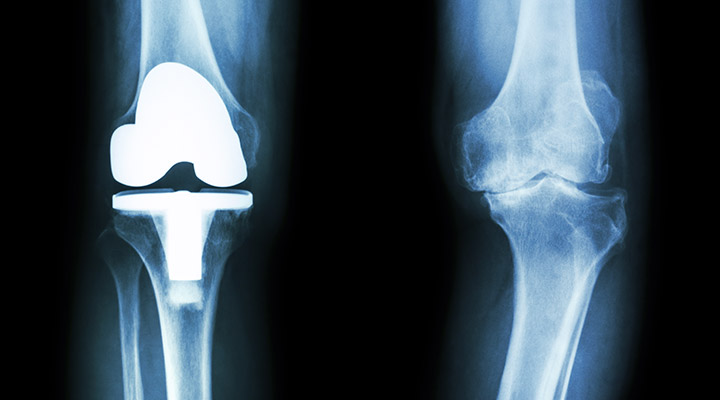

人工膝関節置換術

人工膝関節置換術は、すり減って痛みの原因となっている膝関節の表面(主に大腿骨・脛骨、必要により膝蓋骨)を整え、金属や樹脂(ポリエチレン)の人工関節に置き換える手術です。変形や炎症で生じる強い痛みを軽減し、歩行や日常生活動作を改善することを目的とします。